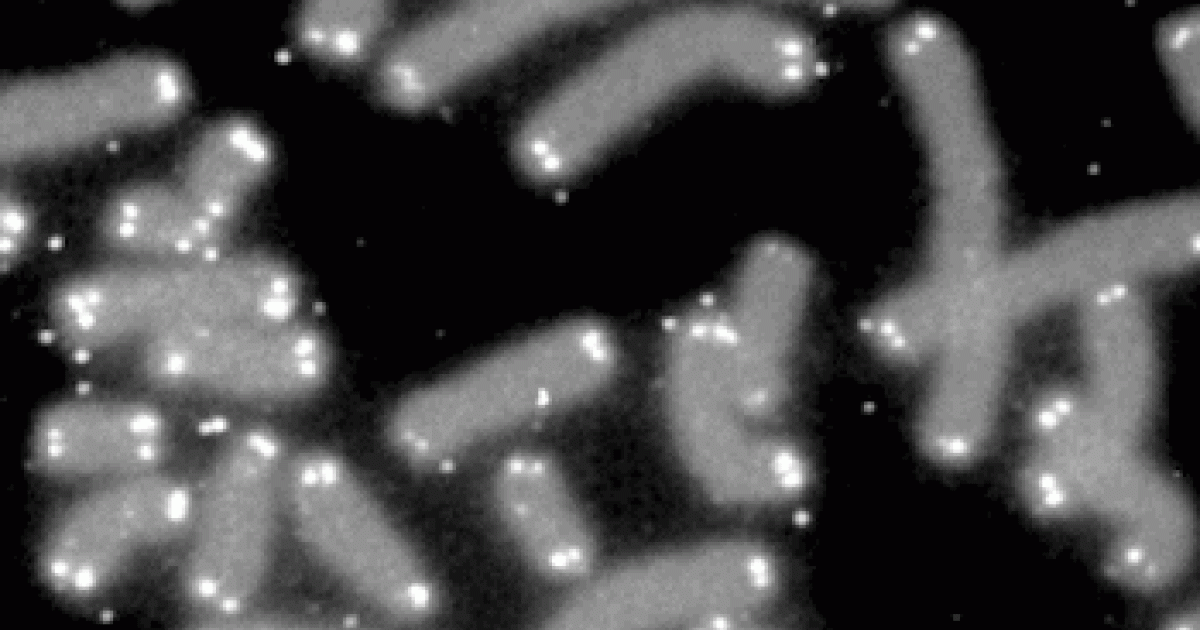

Telomeres play a big role in keeping our chromosomes and bodies healthy even though they make up only a tiny fraction of our total DNA. The Greek origins of the word telomere describes where to find them. “Telo” means “end” while “mere” means “part.” Telomeres cap both ends of all 46 chromosomes in each cell, and protect chromosomes from losing genetic material. They are often compared to the plastic tips at the ends of shoelaces that prevent fraying.

Telomeres get shorter with each round of cell division. Kateryna Kon/Shutterstock.com

Telomeres are important for human health and despite their protective function, they are not indestructible. Telomeres shorten every time a cell divides and shorten progressively as we age.